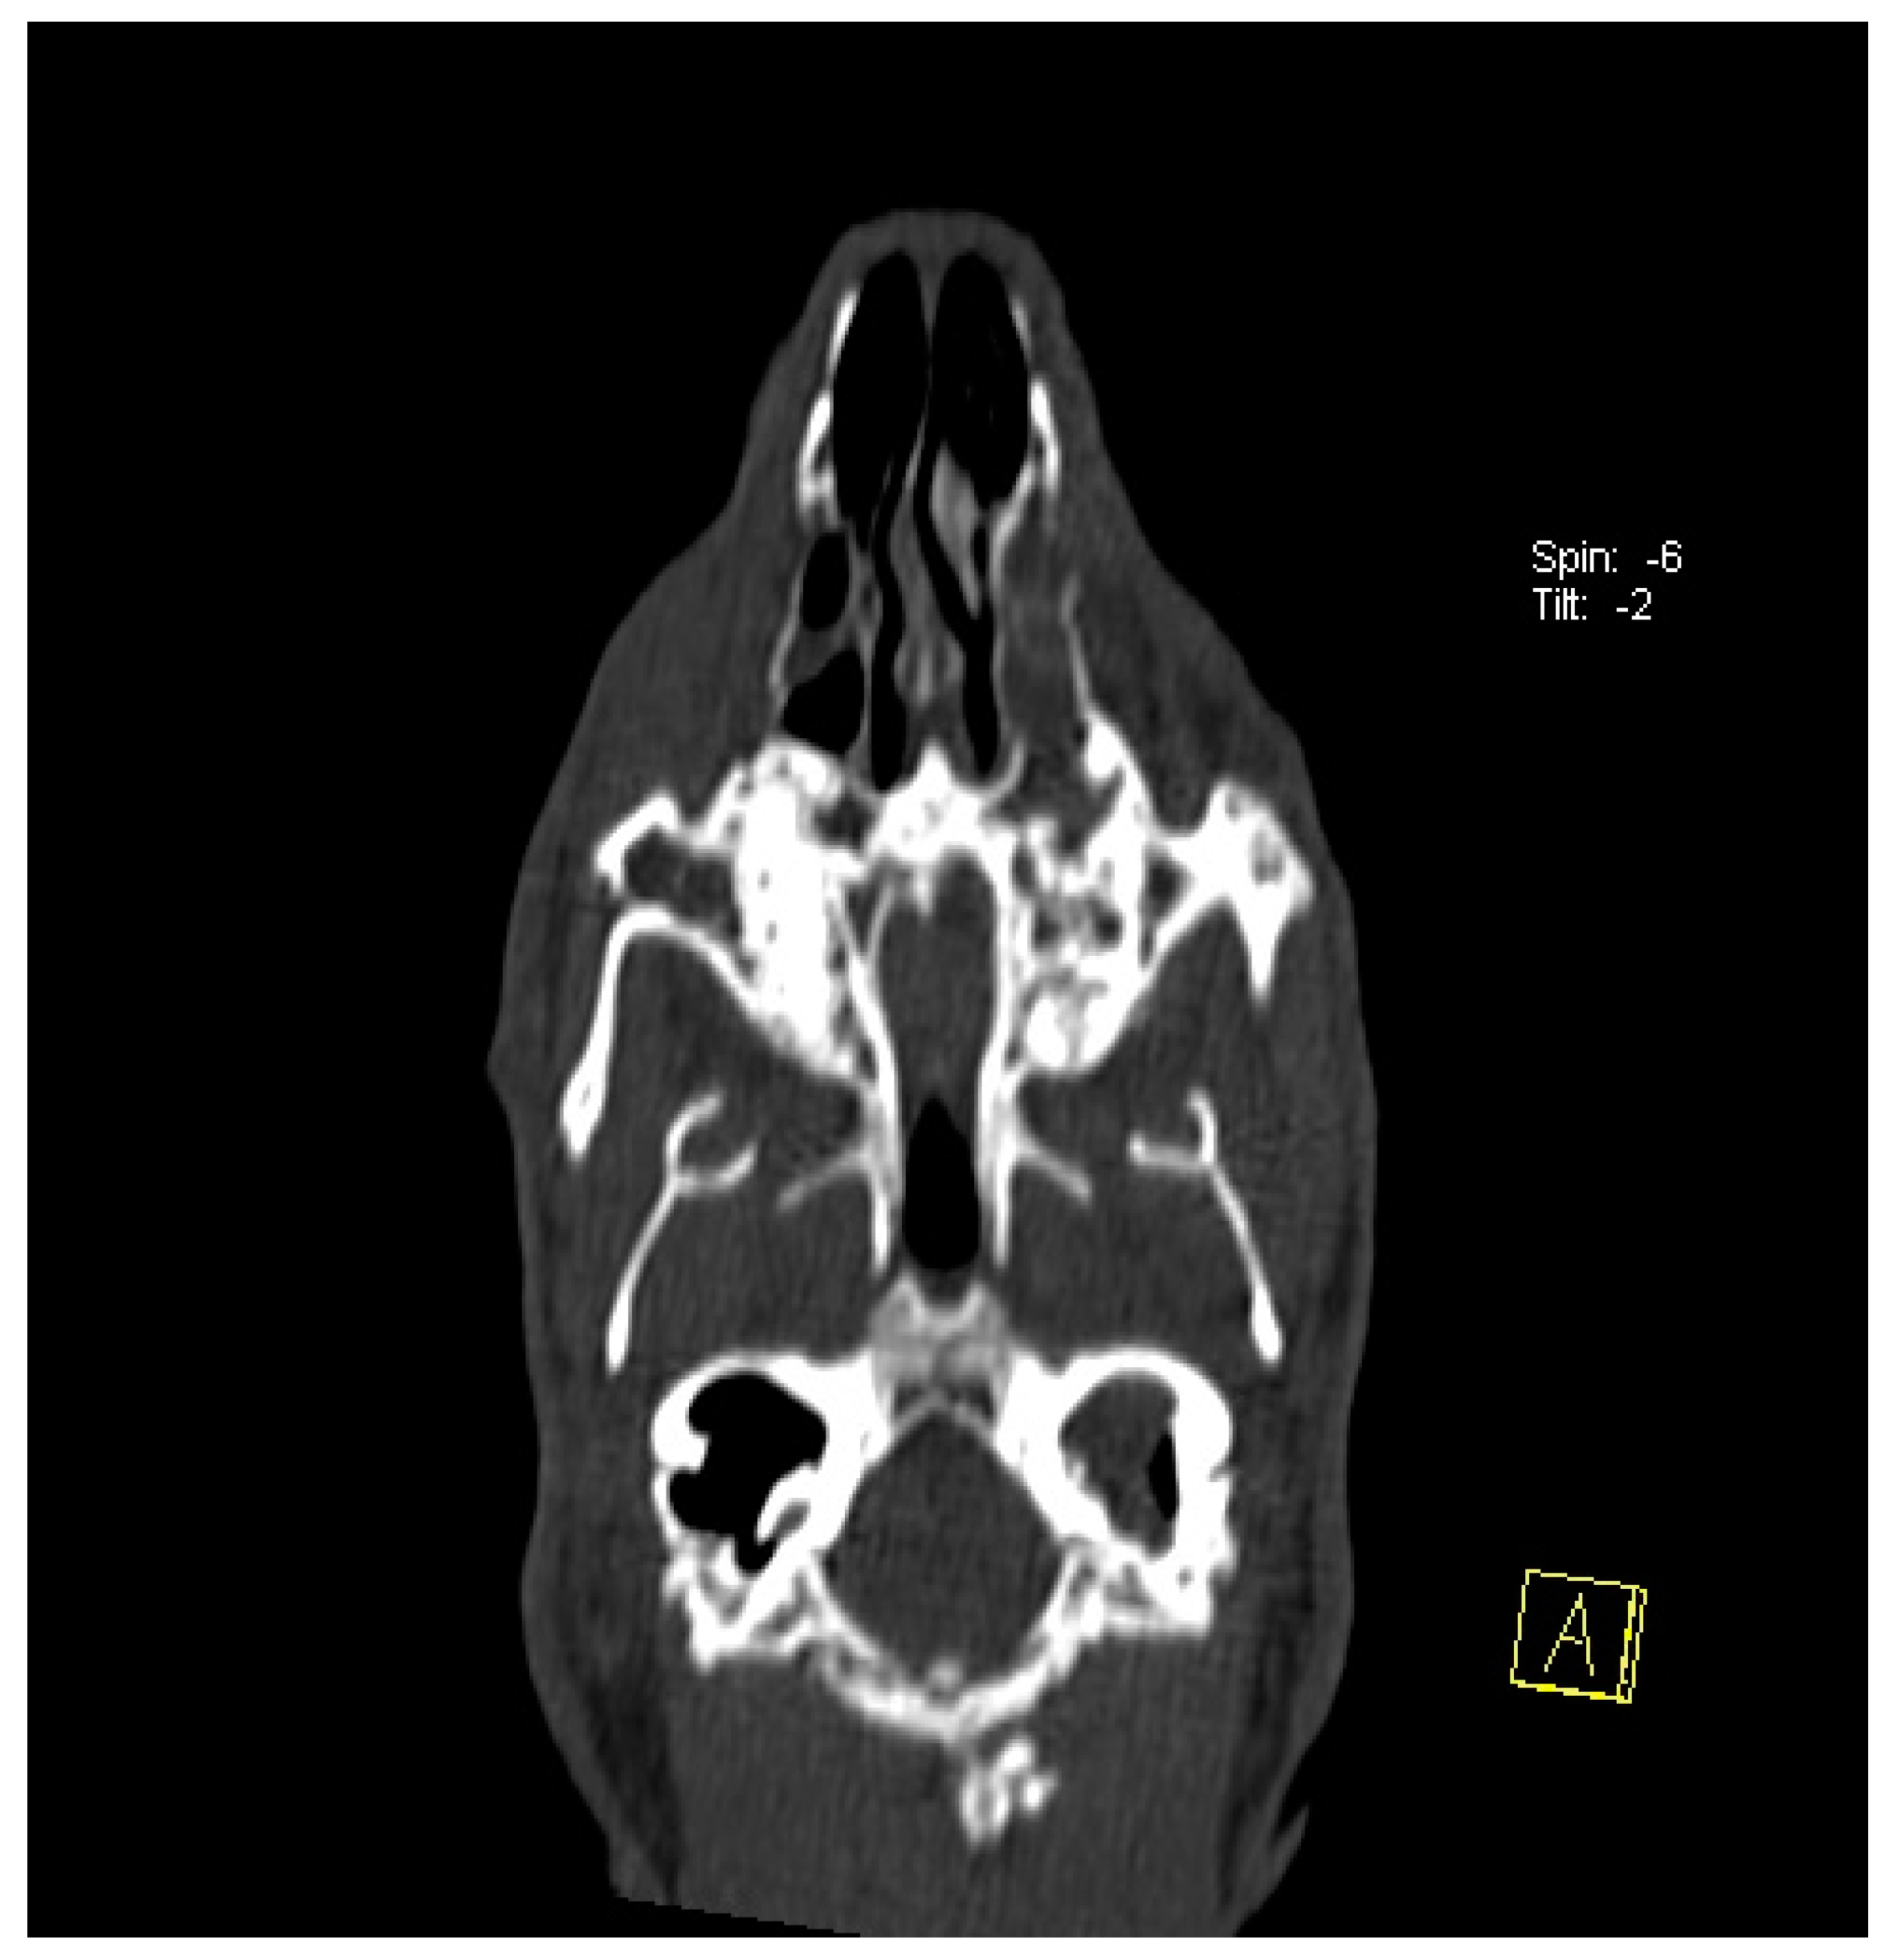

2.4. Computed Tomography of the Head

- Nasal cavities for inflammation secondary to dental disease;

- Tympanic bulla for otitis media secondary to dental disease.